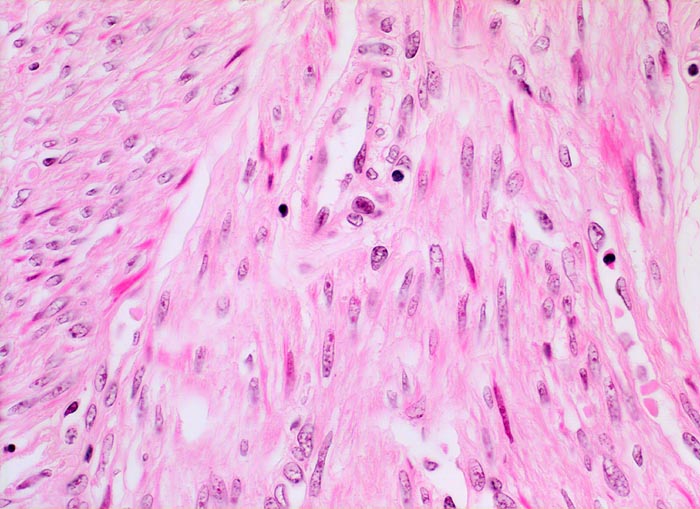

Morphologische Merkmale:

• Zwei scharf begrenzte Knoten im Myometrium bestehend aus Bündeln glatter Muskulatur.

• Variabler Anteil Fibrose (Kollagenfasern).

• Glatte Muskelzelle: eosinophiles Zytoplasma, längliche Kerne mit abgerundeten Enden (zigarrenförmig).

• Keine signifikanten Zellatypien. (signifikant=bereits in der Übersichtsvergrösserung erkennbar).

• Keine Mitosen.

• Keine Tumornekrosen.